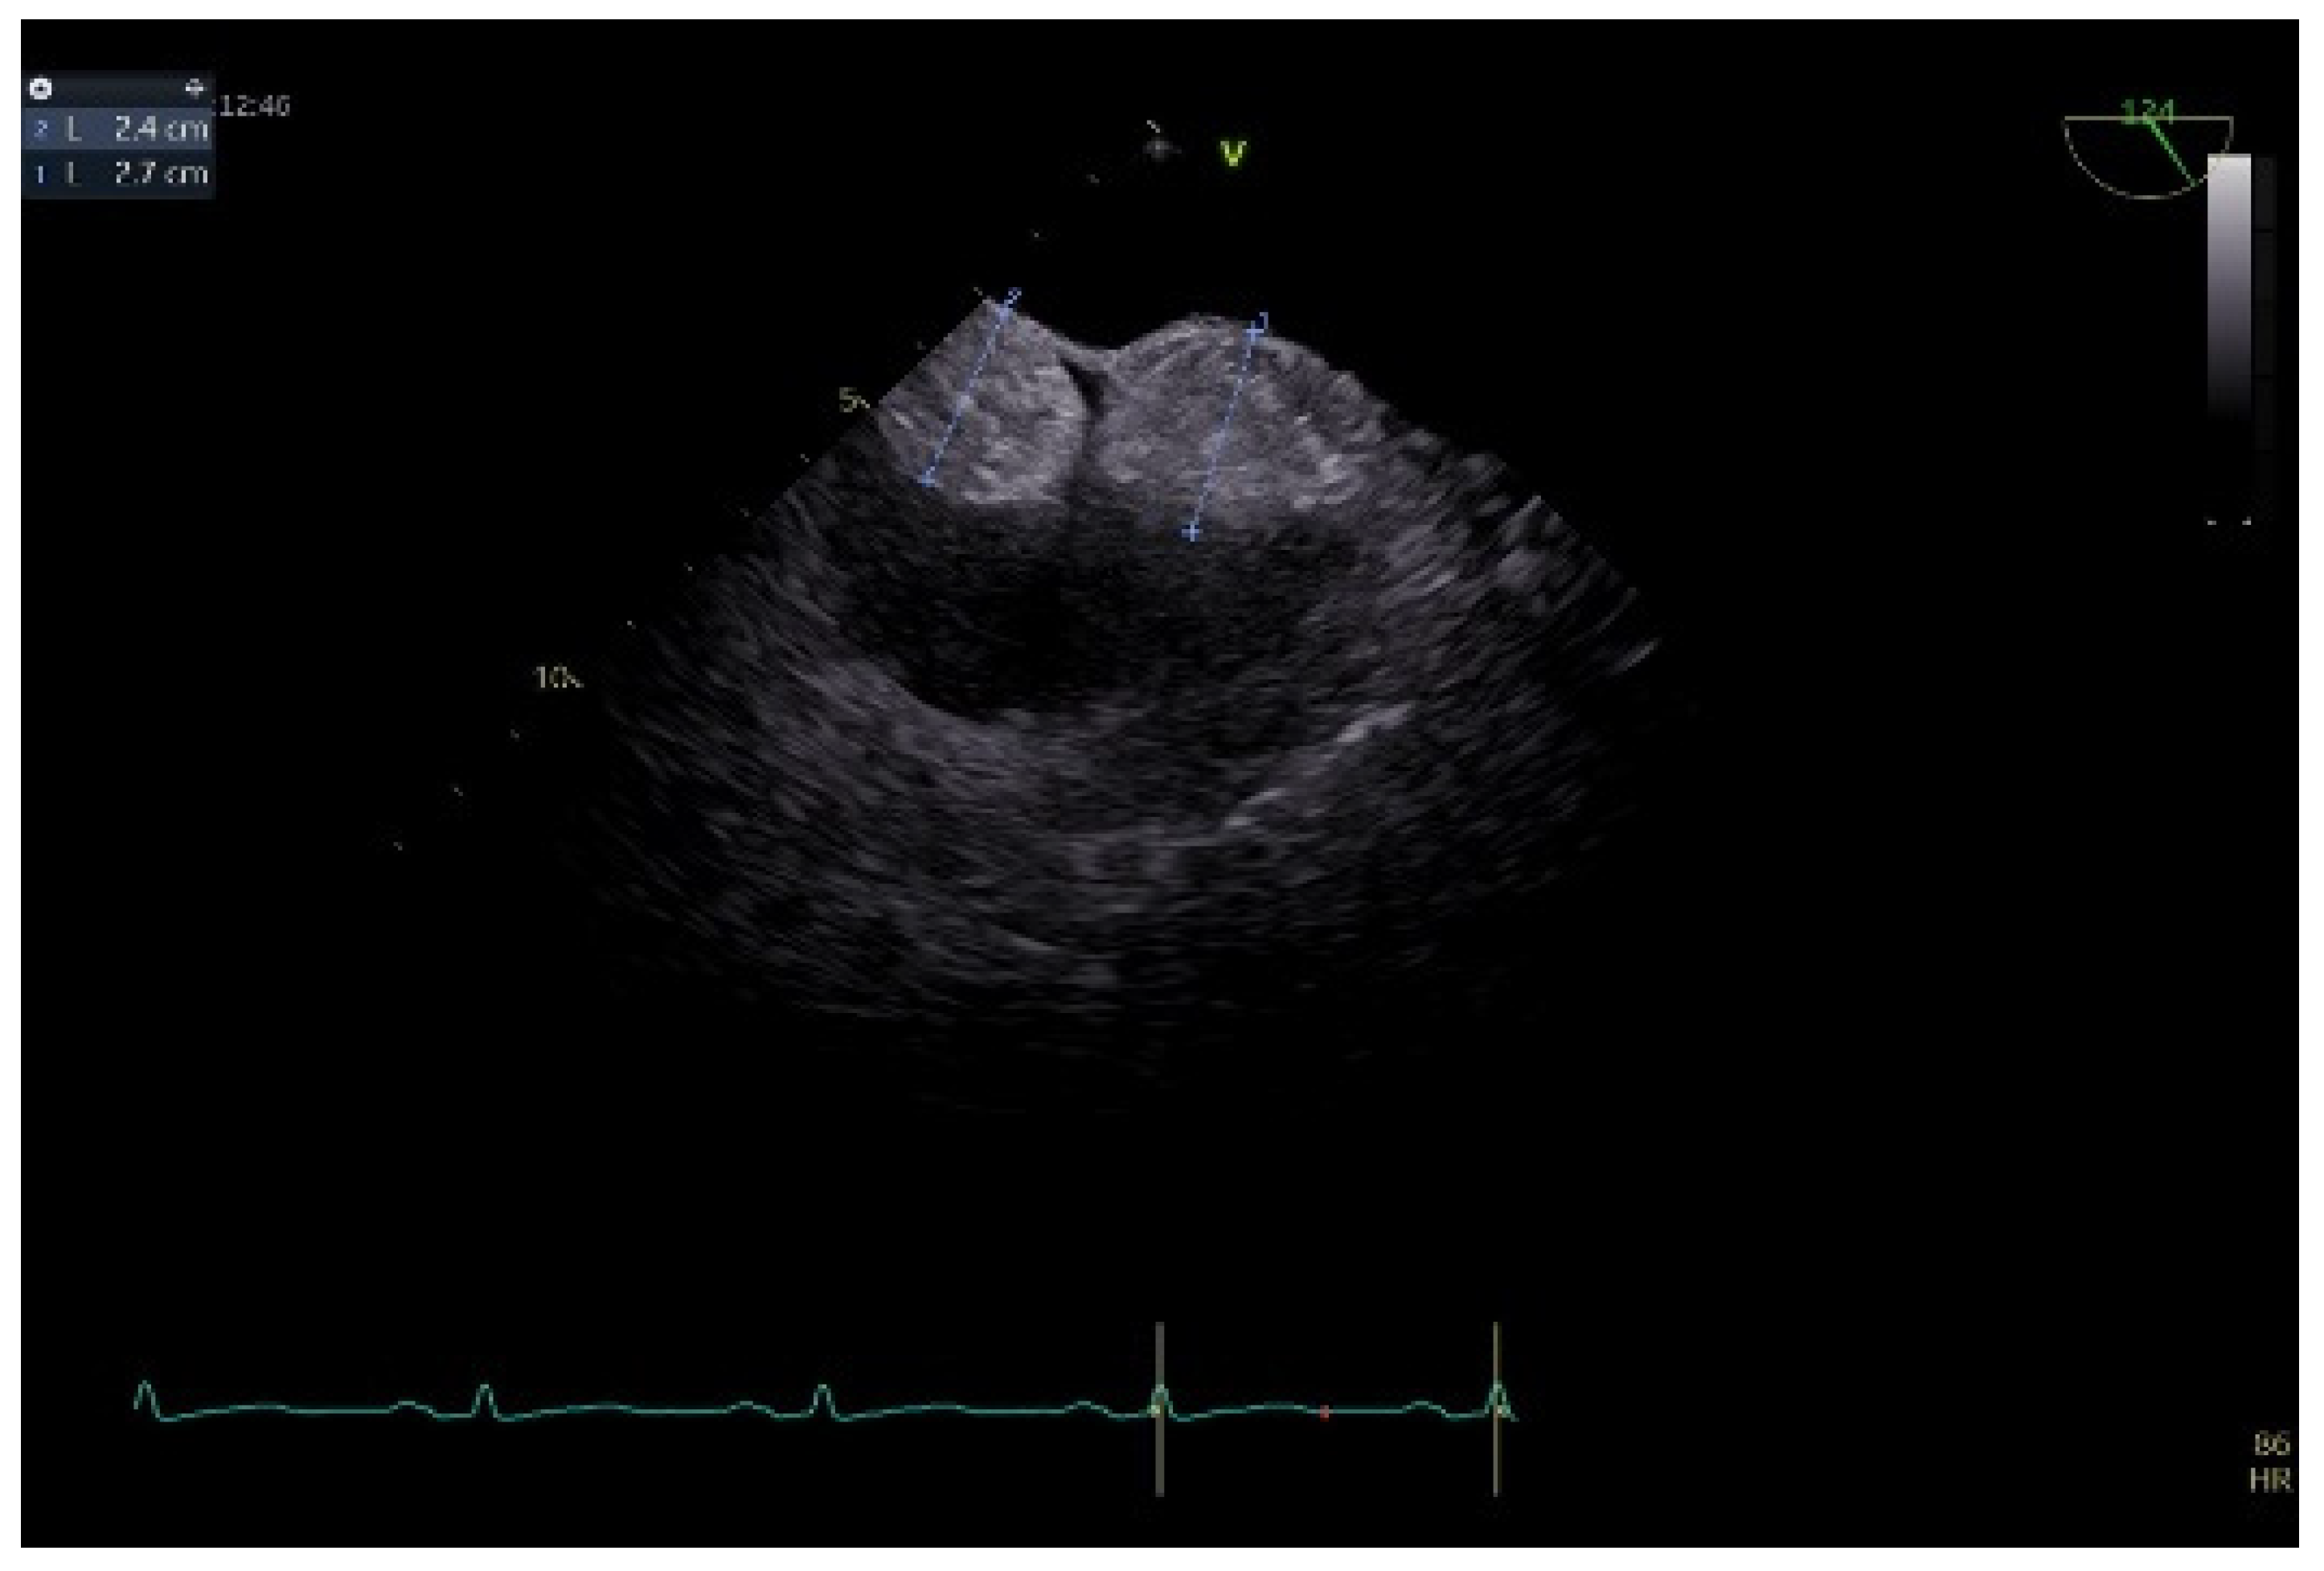

To better describe it, a transesophageal echocardiography was performed. We were surprised to see a second similar so-called mass at the superior pole of the IAS, with the same aspect as described with transthoracic echo. In fact, the IAS was intensely thickened in a diffuse manner except for the fossa ovalis and had the appearance of an “hourglass”, suggesting a possible lipomatous hypertrophy of the interatrial septum. Using both bidimensional (Figure 2) and tridimensional echo (Figure 3), the masses seemed to be encapsulated, homogenous, and attached to the IAS while clearly not being a part of it, aspects that raised some questions in this special patient. There was no color Doppler signal inside the masses, suggesting a lack of vascularization. They lacked any contact and/or continuity with the cardiac valves, an aspect that helped in the differential diagnosis with certain tumors originating on these structures. The right atrial walls were not clearly and entirely viewed. Also, the fact that these masses were not described during previous evaluations was quite unusual. The appearance did not resemble that of a thrombus, since even if the patient had thrombophilia, she was well anticoagulated, and the position and shape of the “masses” did not resemble thrombi. A malignant tumor/metastasis should have been more invasive, irregular, and not respecting the fossa ovalis. The echocardiographic structure of the masses could have resembled a cardiac myxoma though, but possessing two such masses respecting the FO was uncommon. The same situation applies to other possible benign tumors and/or endocarditis. A possible abscess in the context of endocarditis should have also yielded high-inflammation markers. Cardiac amyloidosis was excluded since it did not spare the FO and there were also no other signs of this pathology. Papillary fibroelastoma is usually attached to heart valves, and hemangioma can be found anywhere, most frequently in the LV and RV but also in the RA. Rhabdomyomas are usually found in the ventricular walls and valves, in infants and children. Fibroma is most frequently found in the ventricles, in infants, children, and young adults. Myxoma is normally diagnosed between 30 and 60 years of age, or even earlier if part of Carney syndrome. It can be located anywhere in the heart, but most often within the IAS, pediculated and protruding in the LA. However, a myxoma is a gelatinous non-homogenous mass, due to areas of necrosis and/or hemorrhage, and it sometimes has a villous surface, characteristics that helped exclude this pathology. There are usually multiple malignant tumors which can also be found in any part of the heart. They are irregular masses with an extensive/invasive nature. The most frequent is angiosarcoma which is often located in the RA. Metastatic tumors reach the heart either by direct extension, lymphatic and hematogenous extension, or intracavitary extension through the vena cava and/or pulmonary veins. They are most often secondary disseminations from lung cancer (men) and/or breast cancer (women) [3,7,8,14].

Figure 2.

Bidimensional transesophageal echocardiography, modified bicaval view. Two so-called sessile masses (24–27 mm), at the level of the IAS respecting the fossa ovalis, with the appearance of separate structures.